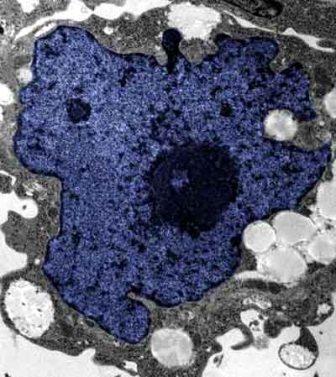

在成人體內(nèi)及胚胎內(nèi)發(fā)現(xiàn)的干細(xì)胞屬于主細(xì)胞,能發(fā)育成各種各樣的組織,可作為人體“修補工具箱”,取代死去及腐壞細(xì)胞組織。此前,最可行的干細(xì)胞為胚胎干細(xì)胞,但它的使用一直受到爭議,因為要在胚胎抽取干細(xì)胞會令胚胎死亡,有人認(rèn)為這樣是變相奪走一條生命。

2007年,日本京都大學(xué)教授山中伸彌為首的科研小組證明,利用病毒倒撥普通皮膚細(xì)胞的“生理時鐘”,可把它們變成像胚胎干細(xì)胞那樣具備“變身”能力的細(xì)胞。但利用病毒把基因輸入細(xì)胞,有可能導(dǎo)致癌癥。這即是說使用這些細(xì)胞的風(fēng)險很大。

來自英國和加拿大的兩組研究員所用的新方法不必使用病毒。這項新突破暗示科學(xué)家現(xiàn)在能更認(rèn)真地看待在醫(yī)學(xué)中利用皮膚干細(xì)胞(即誘導(dǎo)多功能干細(xì)胞,俗稱“iPs”細(xì)胞)的前景。

這些細(xì)胞只要配以適當(dāng)?shù)幕瘜W(xué)品和蛋白質(zhì),就能轉(zhuǎn)化成腦神經(jīng)元、制造胰島素的胰腺細(xì)胞、骨或軟骨、心臟肌肉,或其它多種組織。這些細(xì)胞利用病人皮膚來培育,更暗示它們不會被人體排斥。